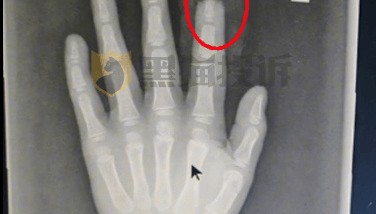

小鹏汽车回应“X9屏幕夹断5岁男童半节食指”

据媒体报道,今年1月,惠州陈先生一家驾驶小鹏X9出行,5岁儿子使用娱乐屏时,左手食指被伸缩支架夹住,...